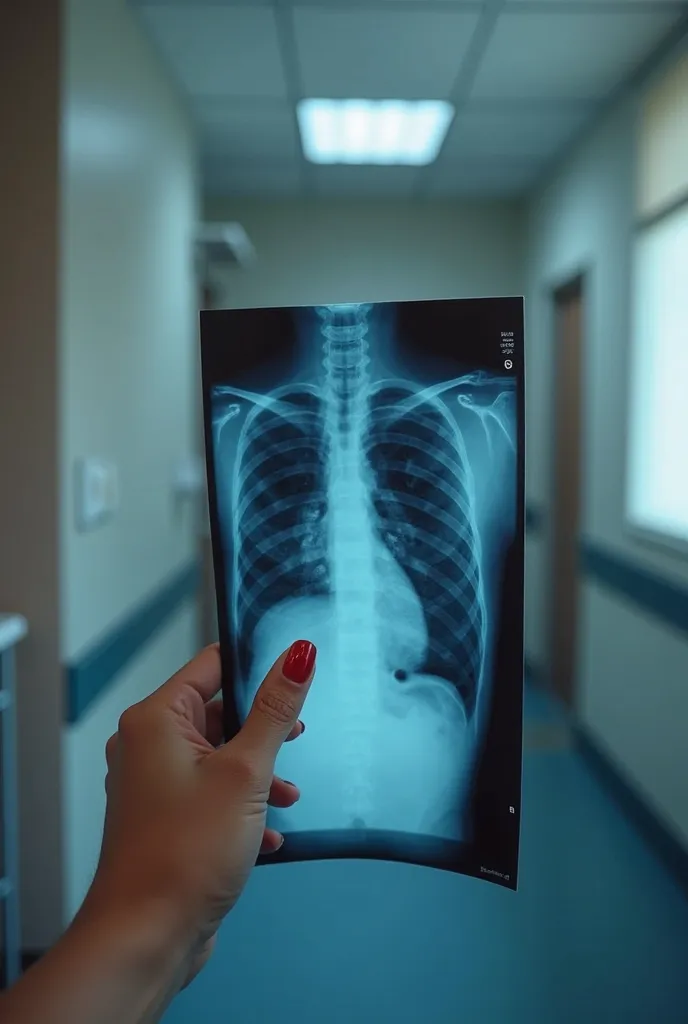

Photo of male doctor looking at lung CT scan , Don't show the face of a doct

Photo of male doctor looking at lung CT scan , Don't show the face of a doctor, hands only

Photo of male doctor looking at lung CT scan

Don'

t show the face of a doctor

hands only